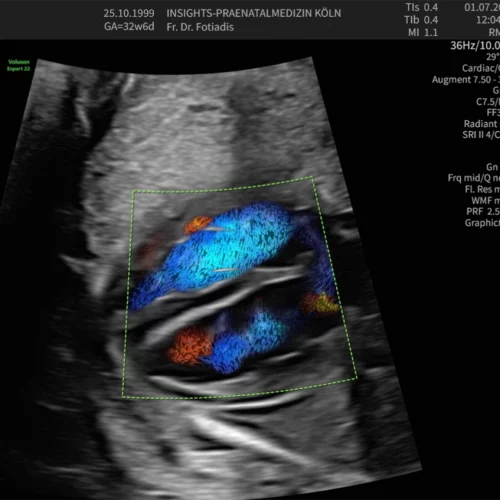

Echokardiographie

Fehlbildungen des Herz-Kreislaufsystems gehören zu den häufigsten Störungen des Neugeborenen und finden sich bei 0,5–1 % aller lebend geborenen Kinder.

Viele dieser Herzfehler sind nicht schwerwiegend und bedürfen keiner Therapie. Ein Teil jedoch kann gravierend, ja sogar lebensbedrohend bei der Geburt sein, sodass hier die Diagnose schon im Mutterleib lebensrettend sein kann. In diesen Fällen muss dann die Entbindung geplant in einem Zentrum mit den Neonatologen und Kinderkardiologen stattfinden, das Neugeborene benötigt bestimmte Medikamente oder muss intensivmedizinisch betreut werden. Manchmal sind auch sehr schnell Eingriffe und Operationen nötig.

Das Entdecken und die Beurteilung von fetalen Herzfehlern erfordert ein hohes Maß an Untersuchungserfahrung und eine entsprechende Geräteausstattung, sodass sie häufig im Rahmen von Routineuntersuchungen nicht erkannt werden. Daher sollten gerade Eltern mit einem erhöhten Risiko für fetale Herzfehler diese Untersuchung des kindlichen Herzens durchführen lassen.